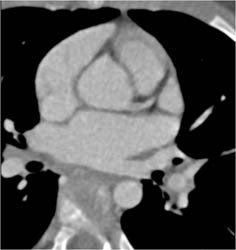

Coarctation of the Aorta